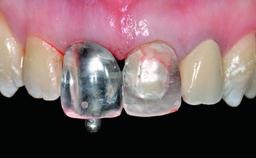

A 15-year-old male patient was referred to us by his pediatric dentist in June 2004 for evaluation of treatment options for his failing tooth 21. The patient had recently seen an endodontist for internal bleaching and been advised that there had been significant resorption and ankylosis. The patient’s mother was concerned because the tooth appeared shorter than the adjacent one. His past dental history was significant for trauma (September 2001), where the tooth had been avulsed and reimplanted. Teeth 11 and 21 had been endodontically treated.